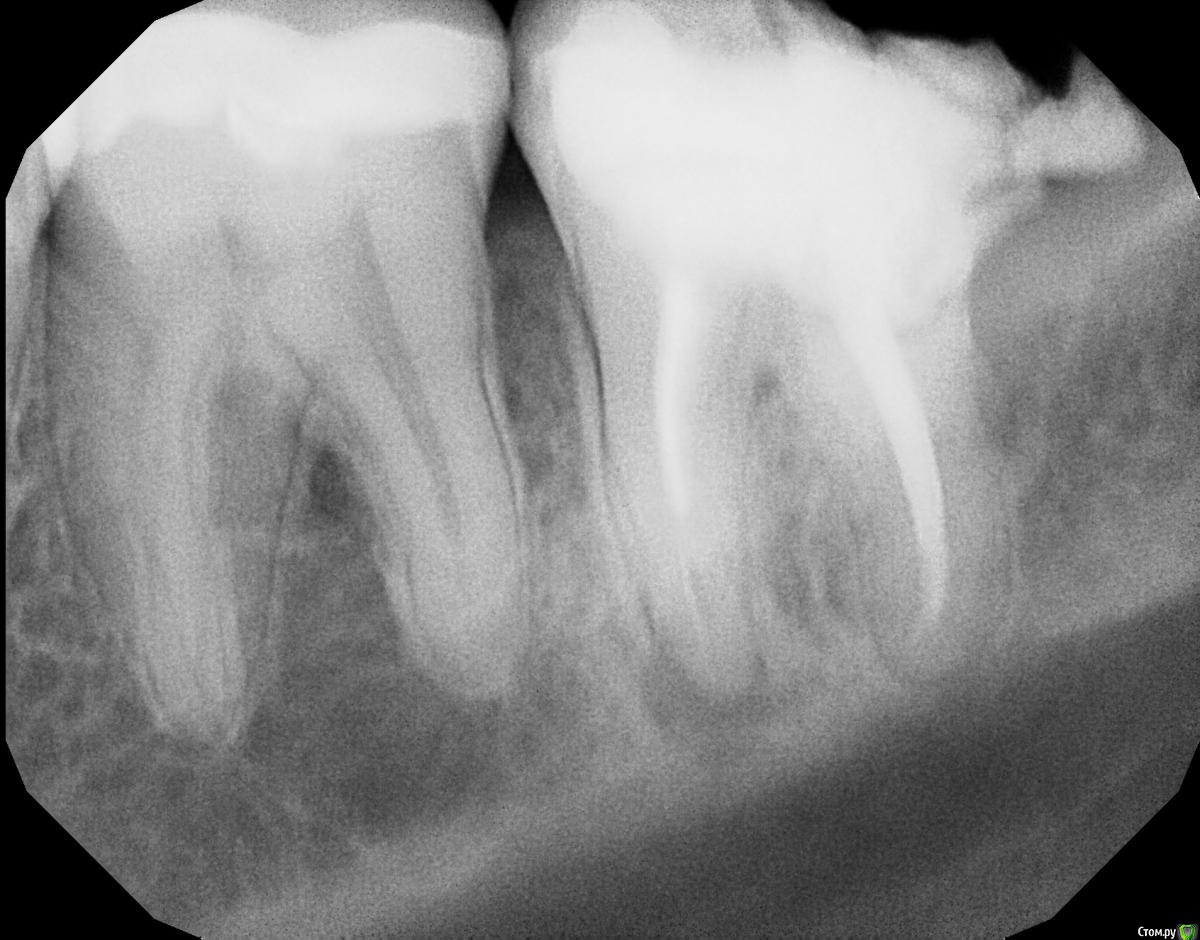

BeardBoy Опубликовано 16 апреля, 2018 Автор Поделиться Опубликовано 16 апреля, 2018 (изменено) Свежий снимок. Зуб был вскрыт, поставлена временная пломба. Возможны варианты сохранения зуба? Целесообразно ли это делать? Изменено 16 апреля, 2018 пользователем BeardBoy Ссылка на комментарий